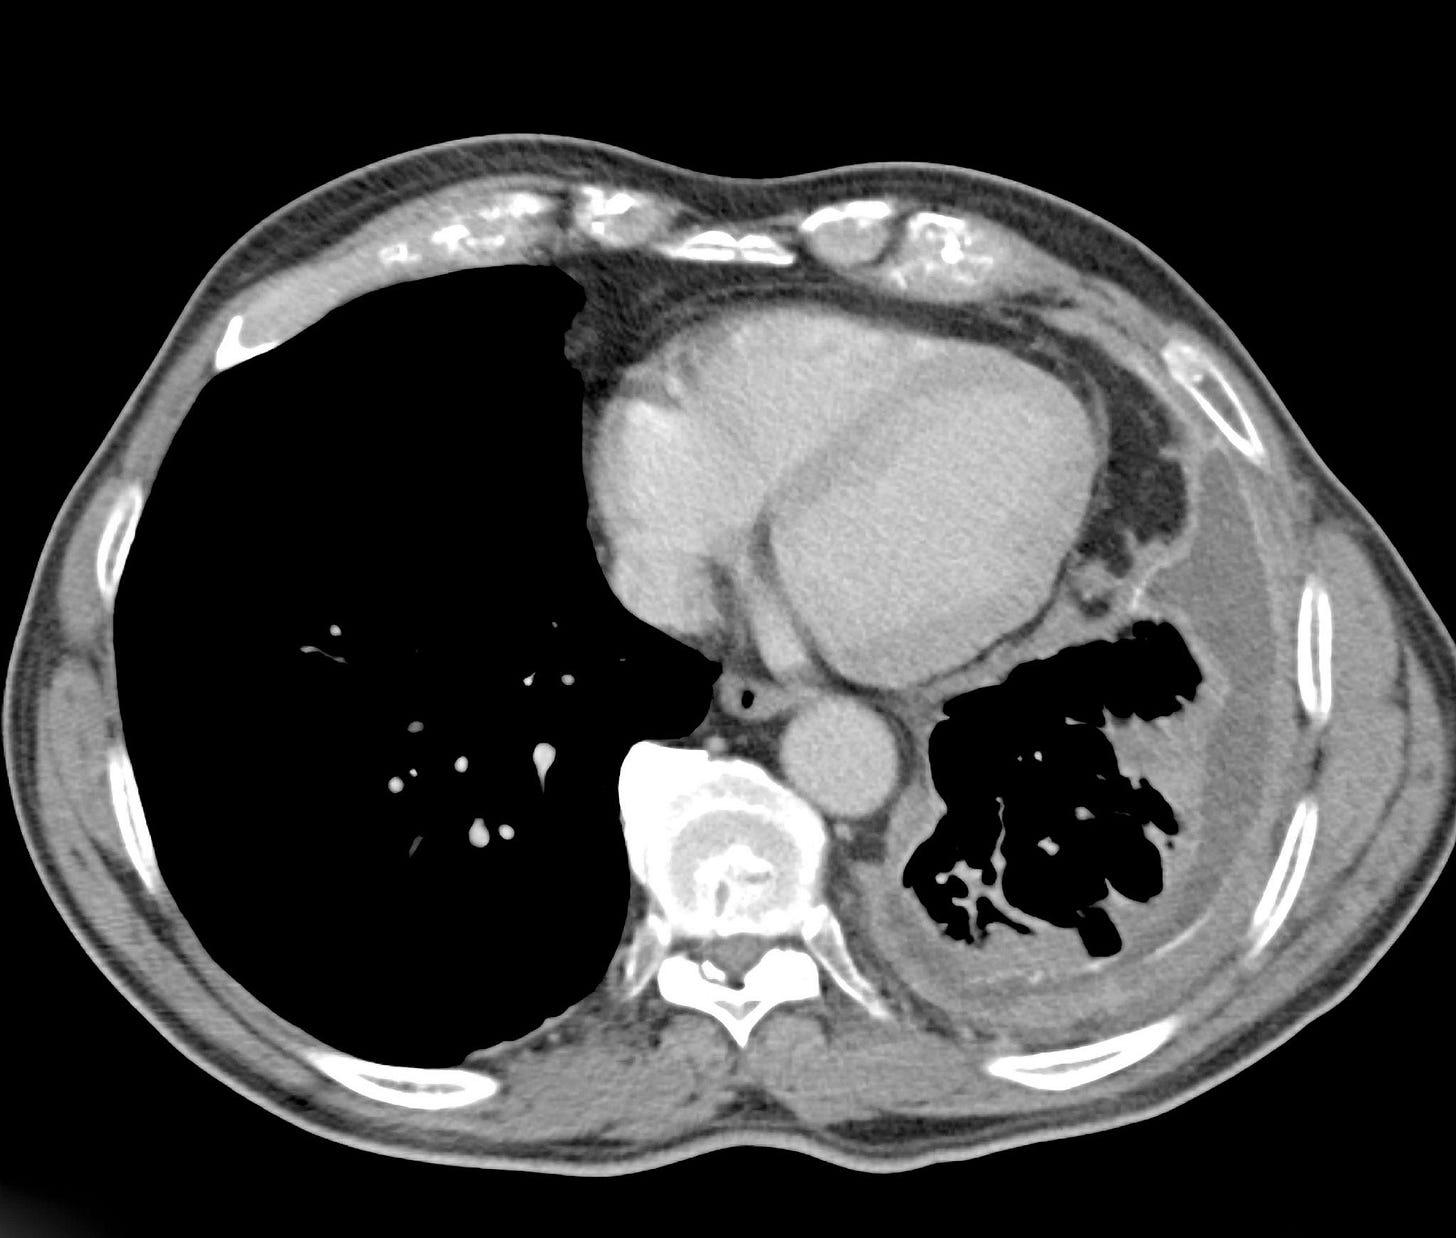

Mesothelioma and Asbestos Exposure

Asbestos was widely used for decades in construction materials, insulation, and industrial products due to its heat-resistant properties. Exposure—often occupational or secondary—has been linked to mesothelioma, lung cancer, and other serious pulmonary diseases such as asbestosis. These diseases typically develop years or decades after exposure, making diagnosis and causation complex. Although asbestos litigation is a mature area of law, it remains highly active, with new claims filed regularly. Recent cases increasingly involve asbestos-contaminated consumer products, including talc. Courts across the country continue to see significant verdicts and settlements in favor of individuals suffering from these devastating illnesses.